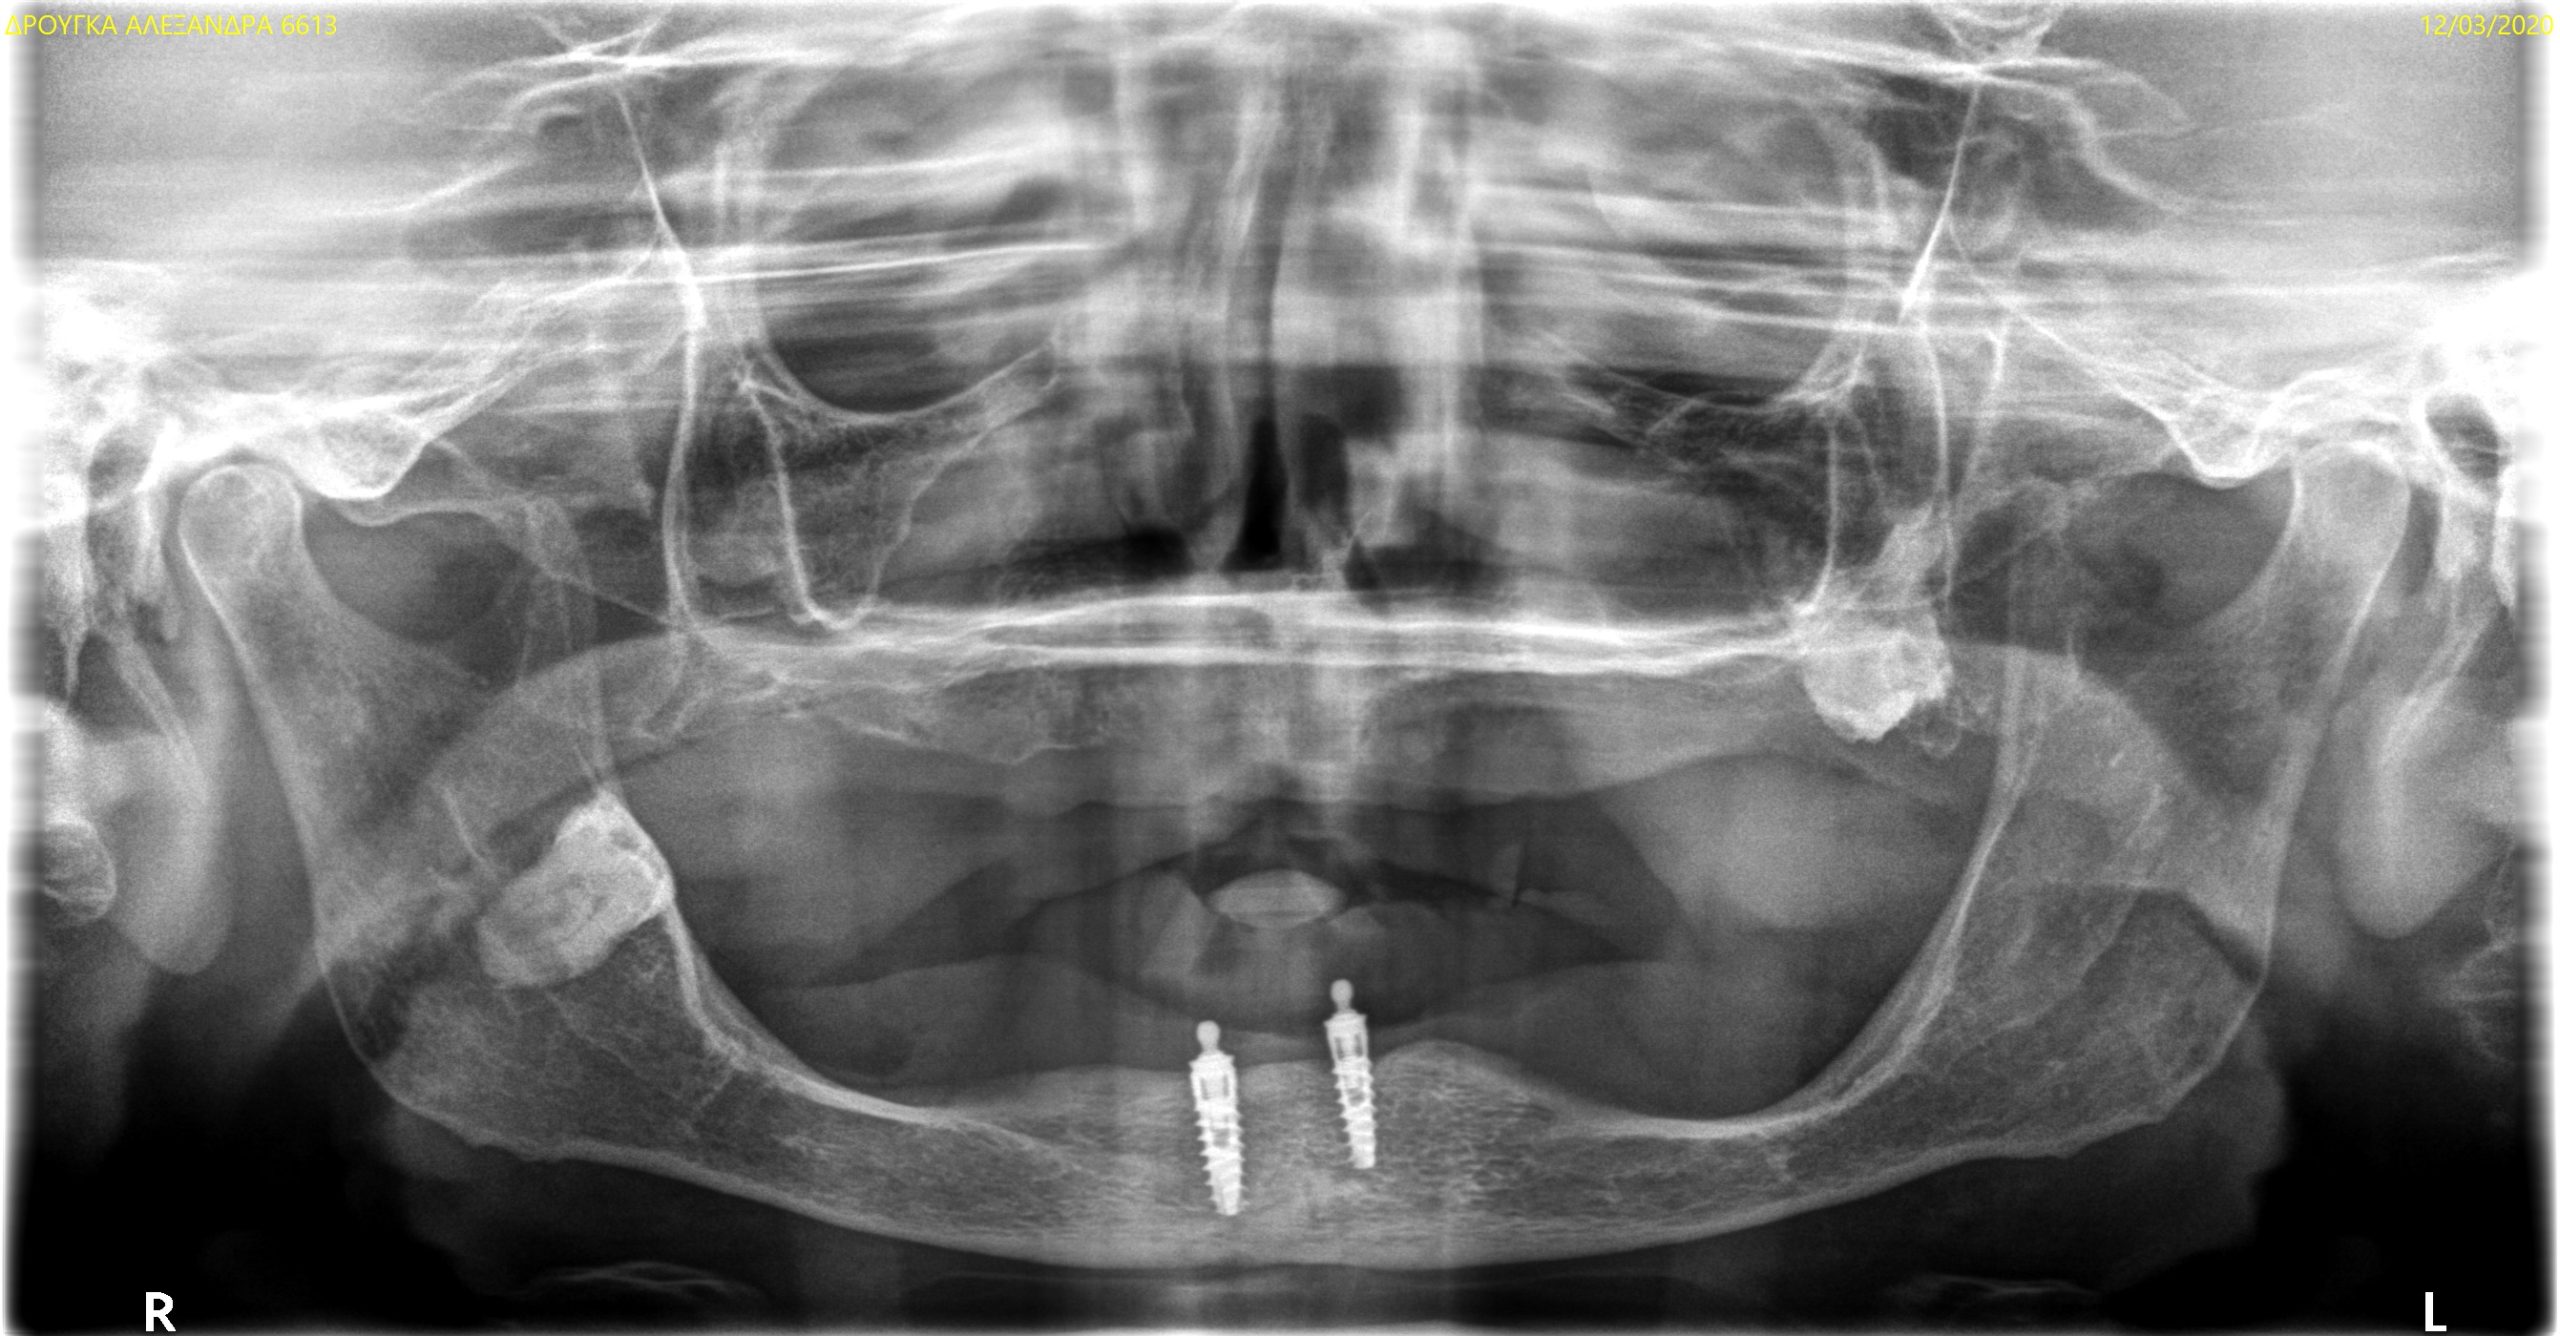

Digital Patient

Complete analysis and digitization of the patient with the aid of state-of-the-art equipment and software.

Implants & Crowns

Prosthetics from traditional impressions and digital files on preparations and implants.